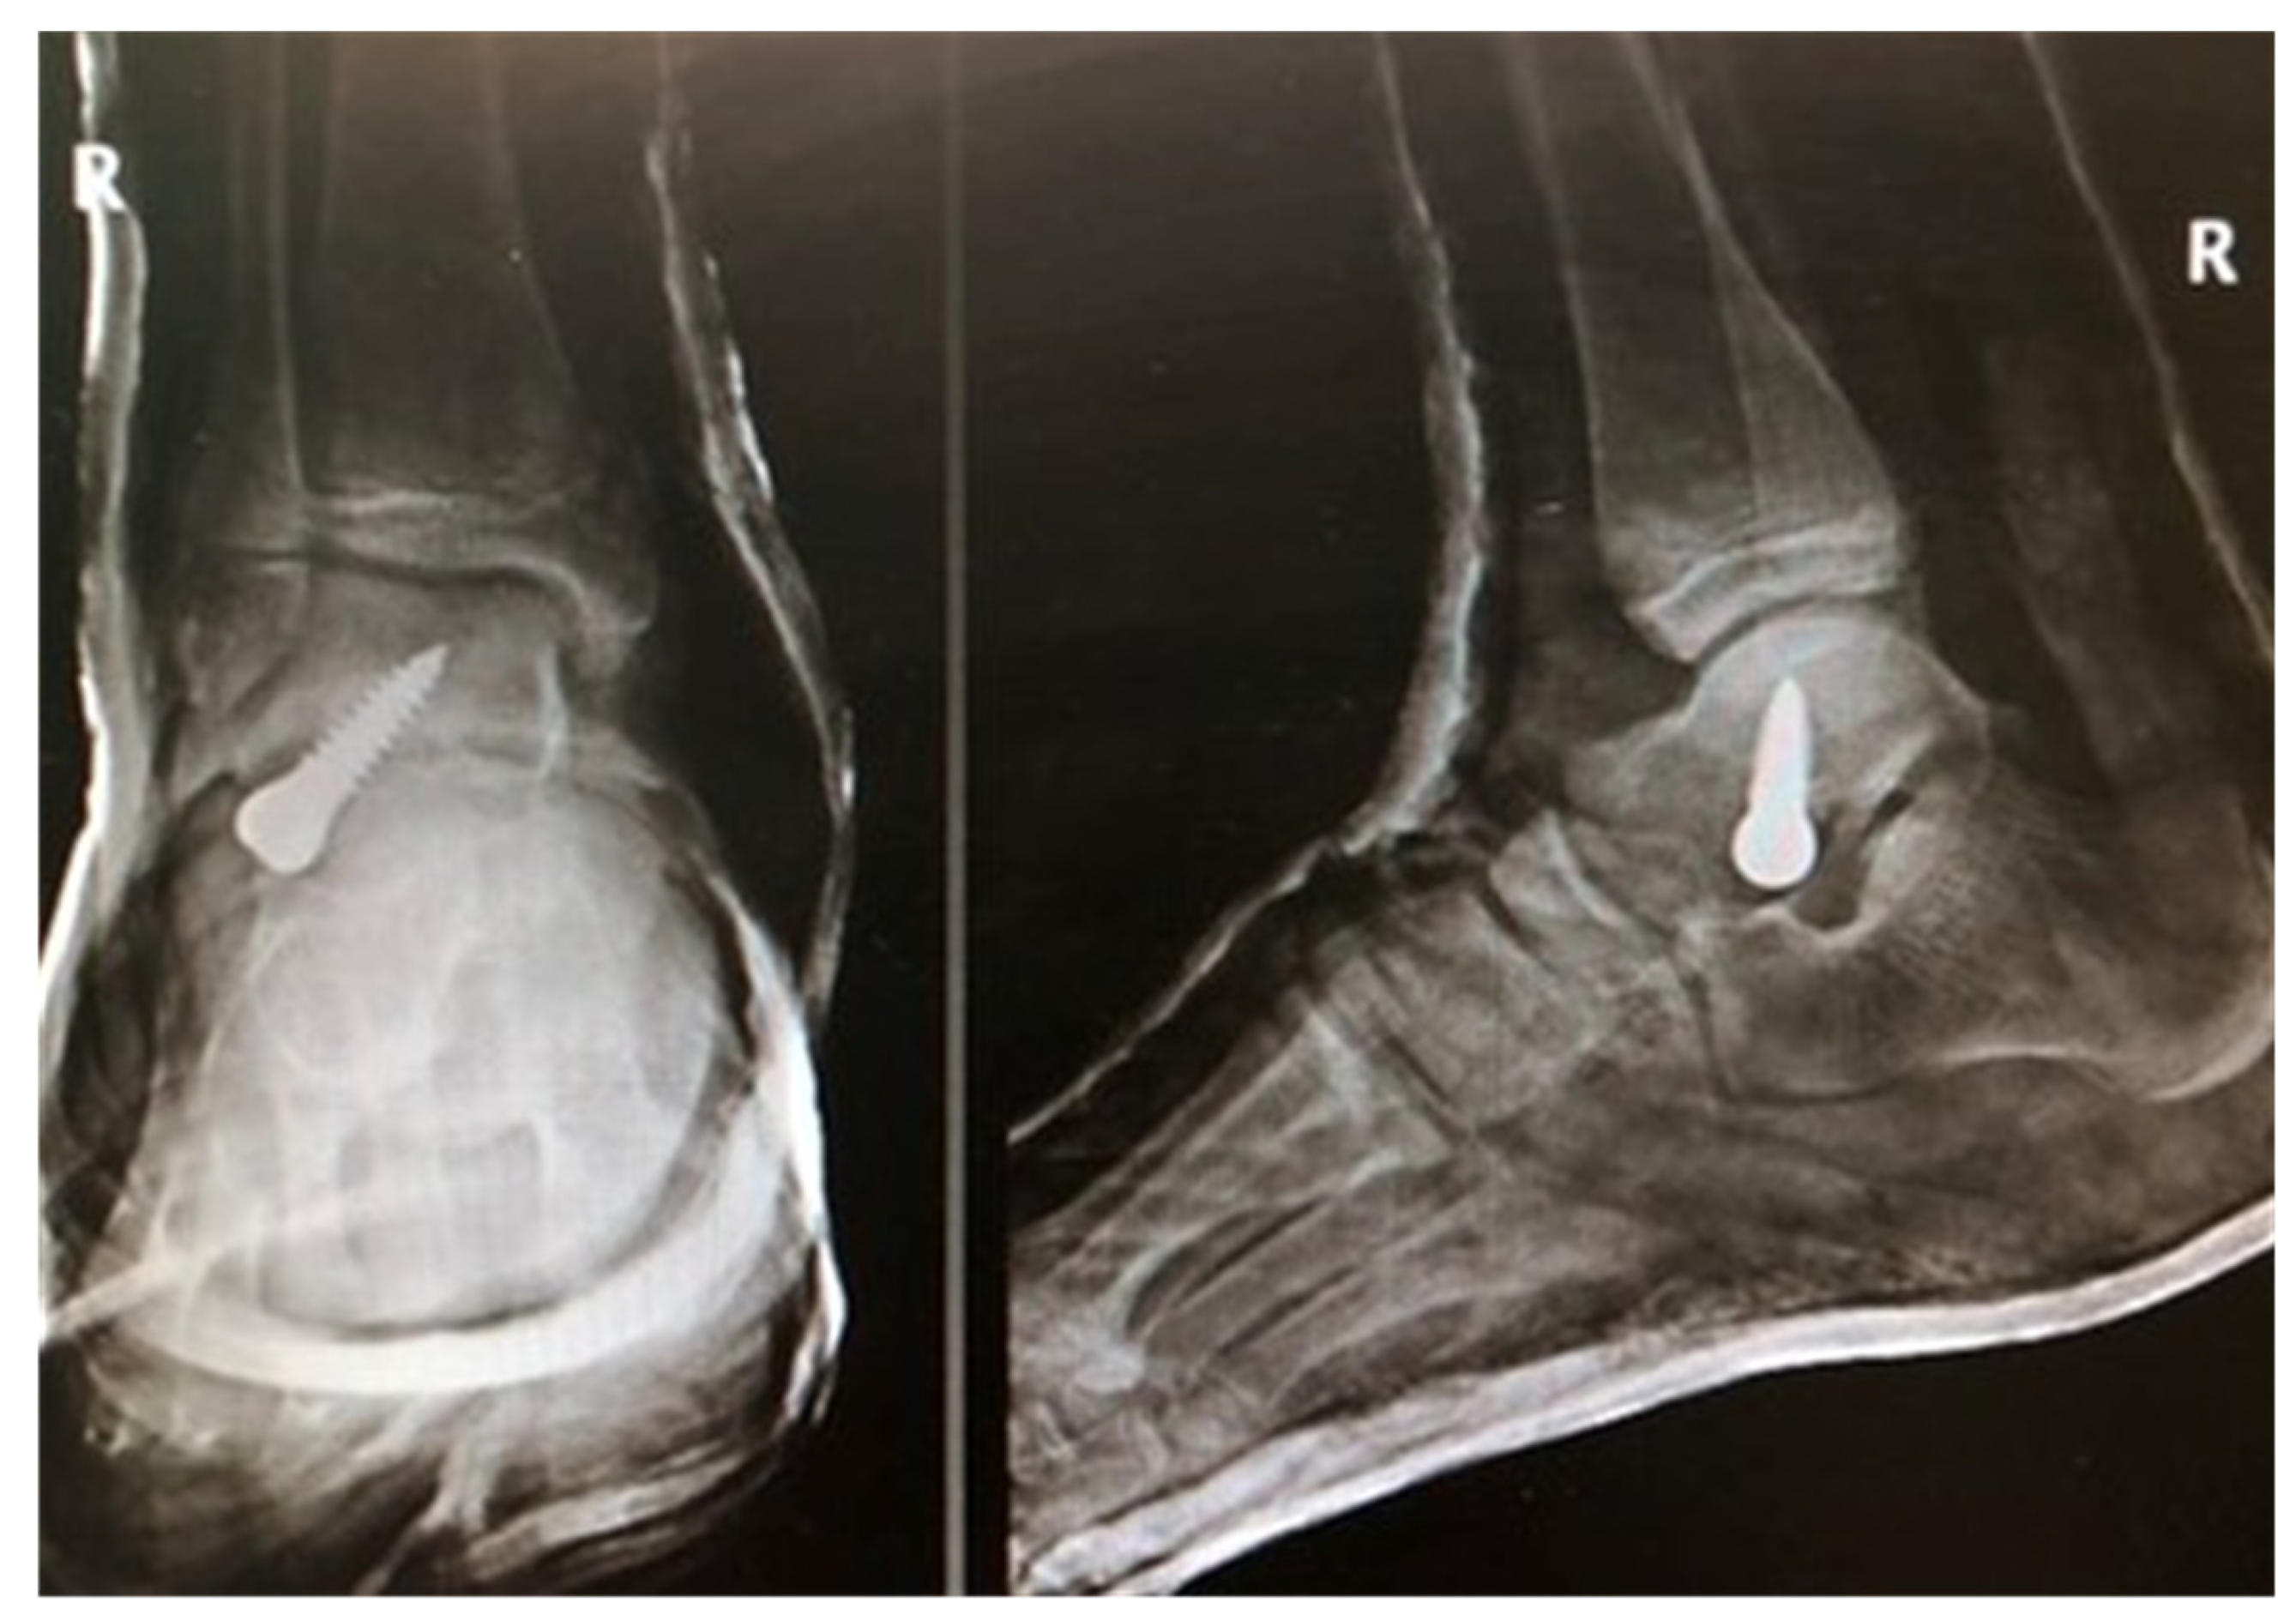

Figure 1.

Radiographic images after pes planovalgus correction with a Spherus screw.